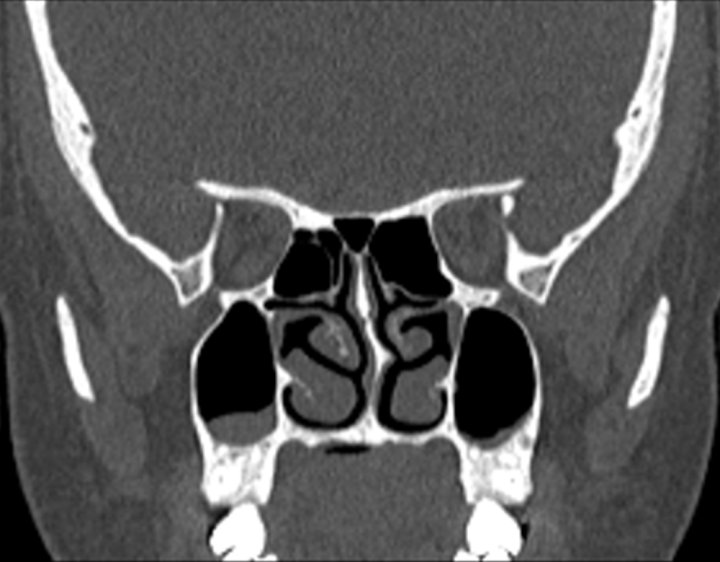

Click any image for labels.